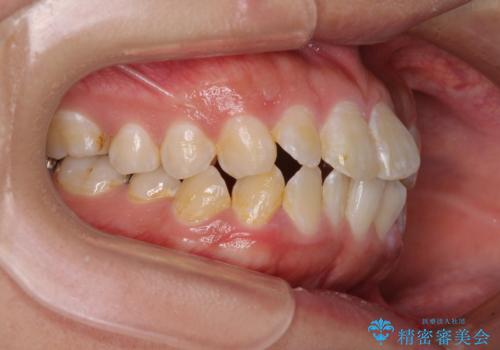

- 前歯のクロスバイトと、口元が閉じにくいとのことで来院された患者様です。

口元の突出感を改善する必要があるため、上下左右の第1小臼歯4本を抜歯し、ワイヤー装置にて矯正治療を行うこととしました。